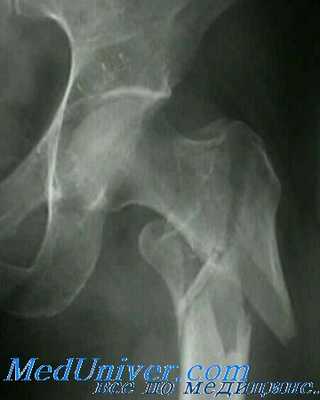

Межвертельные переломы являются внекапсульными и проходят через губчатую кость между большим и малым вертелами. Они обычно встречаются у пожилых больных в возрасте от 66 до 76 лет, у женщин в 4—6 раз чаще, чем у мужчин. Кровоснабжение этой области очень хорошее благодаря тесному прилеганию окружающей мускулатуры и наличию губчатой кости.

Внутренние ротаторы бедра остаются прикрепленными к проксимальному фрагменту, в то время как короткие наружные ротаторы остаются прикрепленными дистальнее головки. Классификацией Boyd и Griffin пользуются большинство ортопедов, однако врачам неотложной помощи достаточно классифицировать эти переломы только на стабильные (I тип) и нестабильные (II тип).

Класс В, I тип: стабильные межвертельные переломы. Единичная линия перелома пересекает кортикальный слой между двумя вертелами. Между диафизом и шейкой бедренной кости смещения нет. Класс В, II тип: нестабильные межвертельные переломы. Между диафизом и шейкой бедра имеется несколько линий перелома или фрагментация с сопутствующим смещением.

Большинство этих переломов является следствием прямой травмы, например при падении на большой вертел или при передаче силы по оси бедренной кости. При воздействии большей силы это повреждение может сочетаться с переломами большого или малого вертела. Мышцы, прикрепляющиеся к вертелам, способствуют дальнейшему смещению фрагментов.

У больного отмечаются болезненность, припухлость и кровоизлияния в области тазобедренного сустава. Обычно наблюдается укорочение конечности с наружной ротацией вследствие тяги подвздошно-поясничной мышцы.

Для выявления этих переломов обычно достаточно снимков в прямой и боковой проекциях.